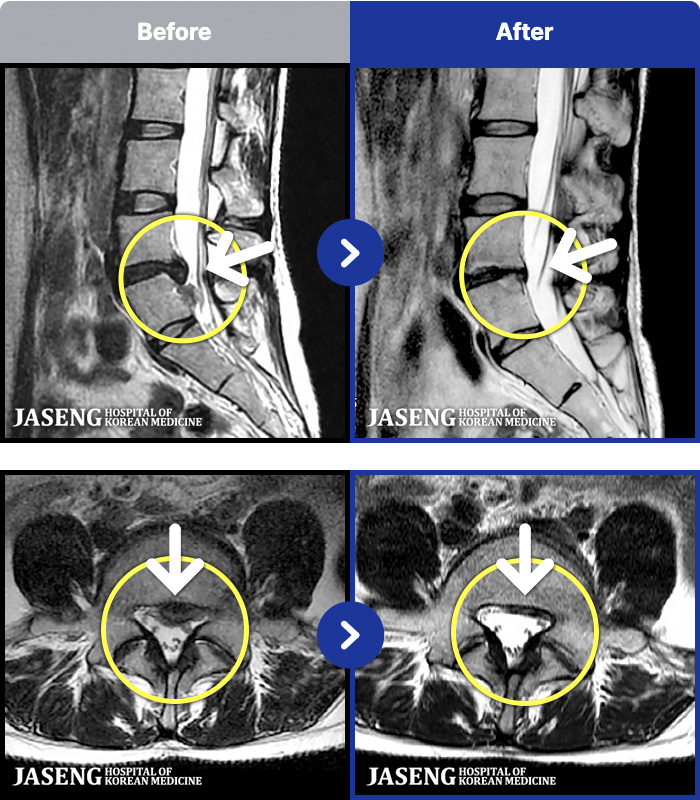

MRI ġ

191 MRI ũ ʸ Ȯϼ.

[Կñ:22.07.16~26.03.17]

[_㸮ũ] 㸮 ٸ ϰ ϻȰ Ұ߽ϴ.